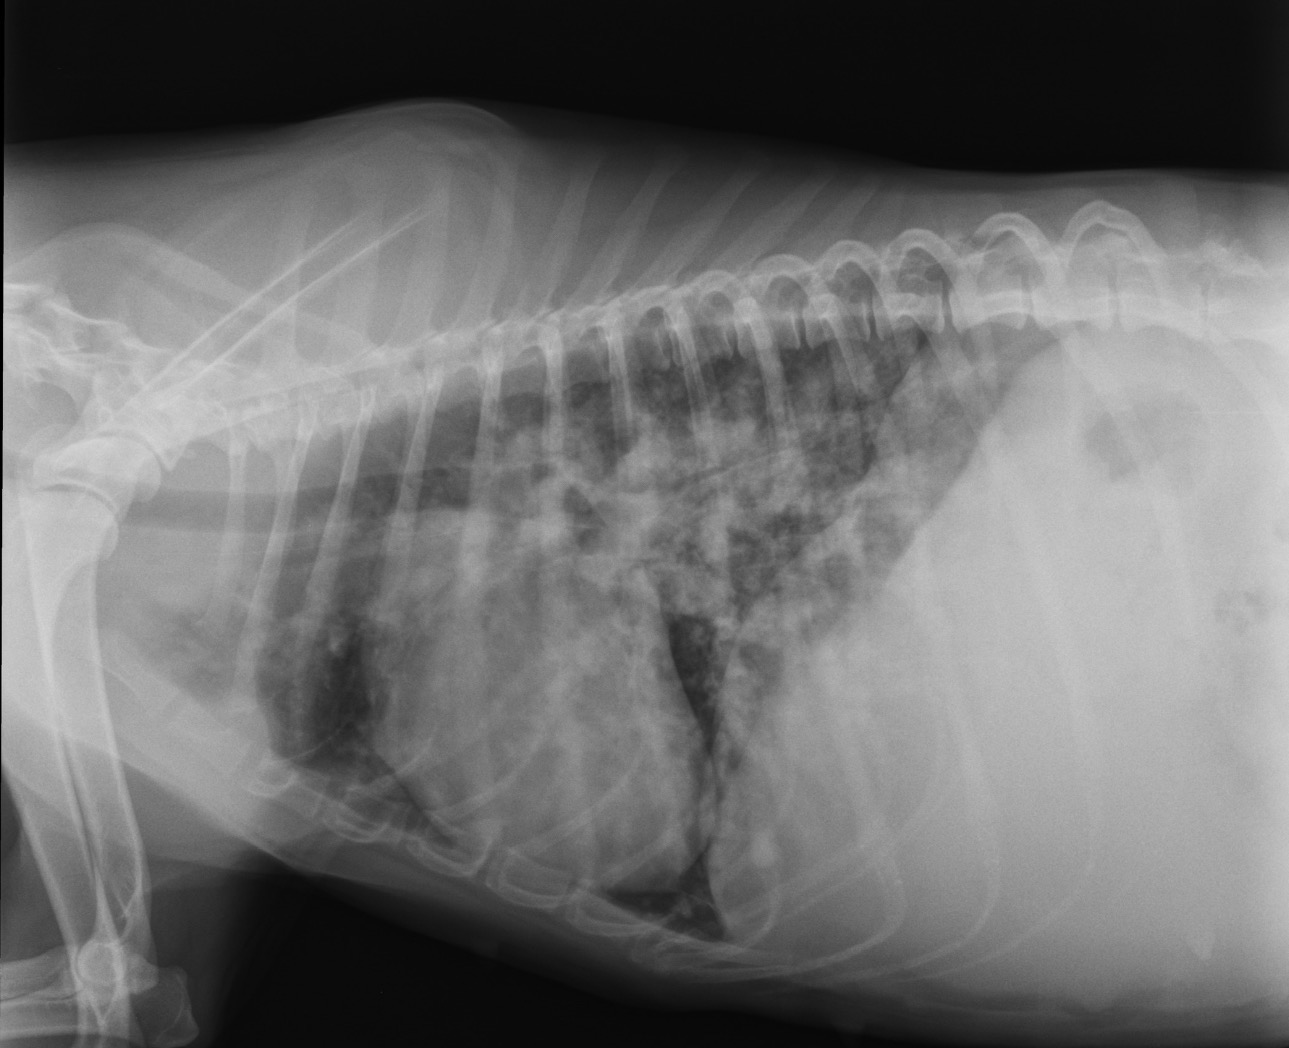

Hola, me llamo Rocío y hace unos meses rescaté a esta preciosa peludita. Había sido abandonada en el campo en muy malas condiciones. Desnutrida, con calvas en el pelaje y prácticamente ciega. Dio positivo en leishmaniosis. Ahora ha dado positivo en filaria en estado muy avanzado, la enfermedad no dio la cara antes. Está ingresada porque tiene muchos gusanos comprometiendo la vena cava, lo que le ha provocado una ascitis por insuficiencia cardiaca. Necesita cirugía de urgencia pero el costo de la operación es elevado. La operación es en Portugal y tiene un costo de 4.000€ más desplazamiento y hospitalización. Estoy a la espera de recibir el presupuesto final.